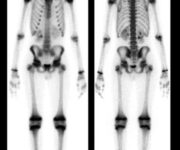

Questo accelerato ricambio, spesso associato a una progressiva riduzione del contenuto minerale (come nell’osteomalacia o nell’iperparatiroidismo secondario), si traduce scintigraficamente in un’assorbimento diffuso e intenso del radiofarmaco in tutto lo scheletro. Questo pattern, noto come “super scan metabolico“, è il segno distintivo di molte di queste condizioni. In un “super scan”, lo scheletro appare straordinariamente ben definito e ipercaptante, mentre l’attività renale e dei tessuti molli è marcatamente ridotta o assente, perché il tracciante viene avidamente assorbito dall’osso.